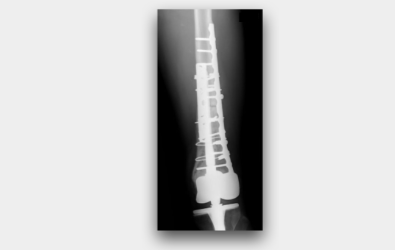

二:手術行腫瘤廣泛性切除。

三:病患的骨骼,以低溫液態氮冷凍治療。同時將軟骨切除,進行人工關節置換。

四:病患手術後X光。可以見得骨骼癒合完全。